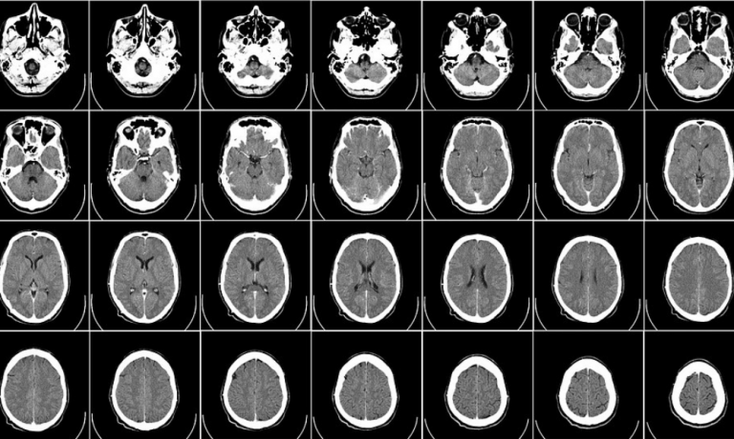

Sometime in the early 2000s, while sitting in my dentist’s chair, I began to wonder about the potential real-world pain that someone could potentially inflict on another human being simply by hacking the new digital x-ray system that the dentist had installed. Would it be possible, for example, for a hacker to modify the digital images from the x-rays so that the dentist would not be able to find and repair painful cavities, or to cause the dentist to perform an unnecessary root canal, filling, or other procedure? How certain could I be that the images of my own teeth were not tampered with? Several years later, when I had my a digital MRI after an auto accident, I wondered even further – could hackers modify images in such a manner so as to cause a person to have his head cut open to remove a tumor when, in fact, he had no tumors? Or to cause a scan to appear normal when the victim actually had a life threatening condition requiring immediate attention? This past week, a report issued by a combined team of researchers from the Department of Information Systems Engineering at Ben-Gurion University in Beersheba, Israel, and the Soroka University Medical Center nearby, answered the question in a clear – and quite frightening – way: Not only can hackers using Artificial Intelligence (AI) technology successfully and consistently trick radiologists in ways that could potentially lead to human deaths, but evildoers can even trick artificial intelligence systems designed to diagnose medical conditions based on scans. In the recent study, the Israeli researchers used a Generative Adversarial Network (GAN), a form of machine learning system that can generate photographs that look at least superficially authentic to human observers, even though the images are nothing more than sophisticated, high-resolution computer drawings of non-existent people or landscapes. The researchers trained one GAN to add cancer into scans that showed no cancer, and another to remove cancer from scans that showed it. They then trained their engines to add or remove specifically lung cancer, by letting the systems learn from free online medical images. They then hired 3 radiologists to read 100 scans: 30 authentic CT scans, and 70 that were modified by the AIs. The results are downright scary: The radiologists found cancer in 99 percent of the AI-altered normal scans that had malignant tumors added to them by the GAN, and found no cancer in 94 percent of the images from scans that showed cancer, but which had the cancer removed by the second GAN. Even after the researchers told the radiologists about the GANS, and informed the doctors that many of the images had been tampered with, the radiologists were still unable to diagnose correctly, and incorrectly found cancer in 60 percent of the normal scans to which tumors had been artificially added, and did not find cancer in 87 percent of the scans from which the AI had removed tumors. Artificial Intelligence systems designed to diagnose diseases from scans did not fare any better. How hard would it be for an evildoer to manipulate images in order to perpetuate insurance fraud, or to inflict physical harm to another human being? For insiders who have access to the imaging systems, such crimes would likely be simple to carry out. But, even for outsiders, the barriers are quite weak: While many MRI and CT scan systems are not connected to the Internet, getting physical access to the terminals used to manage images from these systems is not difficult. Whether by putting on a lab coat and impersonating a doctor, pretending to be an IT support person fixing a computer, or through a whole host of other social engineering type acts, it is not hard to get access to relevant hospital terminals for long enough to insert a device into a USB port. And, of course, as time progresses, a growing number of systems are, in fact, connected to the Internet – creating the potential for remote attacks. Of course, hospital WiFi networks may serve as a potential entry point as well. Clearly, the entire medical imaging ecosystem needs better security. Requiring the use of security software on any device that is any way involved in the imaging process, as well as mandating that all imaging systems use encryption and digital checksums (and/or watermarks) on images, and securing the infrastructure used by imaging-related processes, might go a long way in preventing what otherwise could ultimately emerge as a potential way to commit all sorts of crimes – even murder.